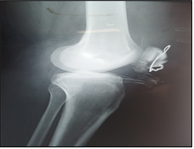

After a decline of six months (Figure 1), we identified one (01) case of pseudarthrosis or 5.88% and one (01) case of patellofemoral osteoarthritis or 5.88%.

(a) (b) (c) (d)

Figure 1. (a) Fracture of the patella, Duparc type II; (b and c) osteosynthesis by cerclage; (d) knee flexion at six months.